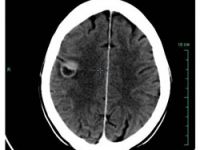

Ölümcül beyin tümörüne karşı aşıEn ölümcül beyin tümörlerinden glioblastoma hastalarının yaşam süresini yüzde 70'den fazla uzatan bir aşı geliştirildi.05 Ekim 2010 Salı 10:25